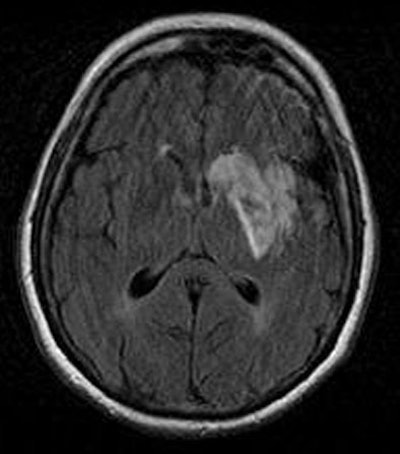

![]() |

| Diffusion-weighted image as well as fluid-attenuated recovery T2-weighted images obtained two days after the initial perfusion CT and MRI demonstrate a hyperintense area close to that on the perfusion CBF and MTT maps and the initial diffusion-weighted imaging. A slight penumbra loss is demonstrated. Images courtesy of Dr. Sotirios Bisdas. |